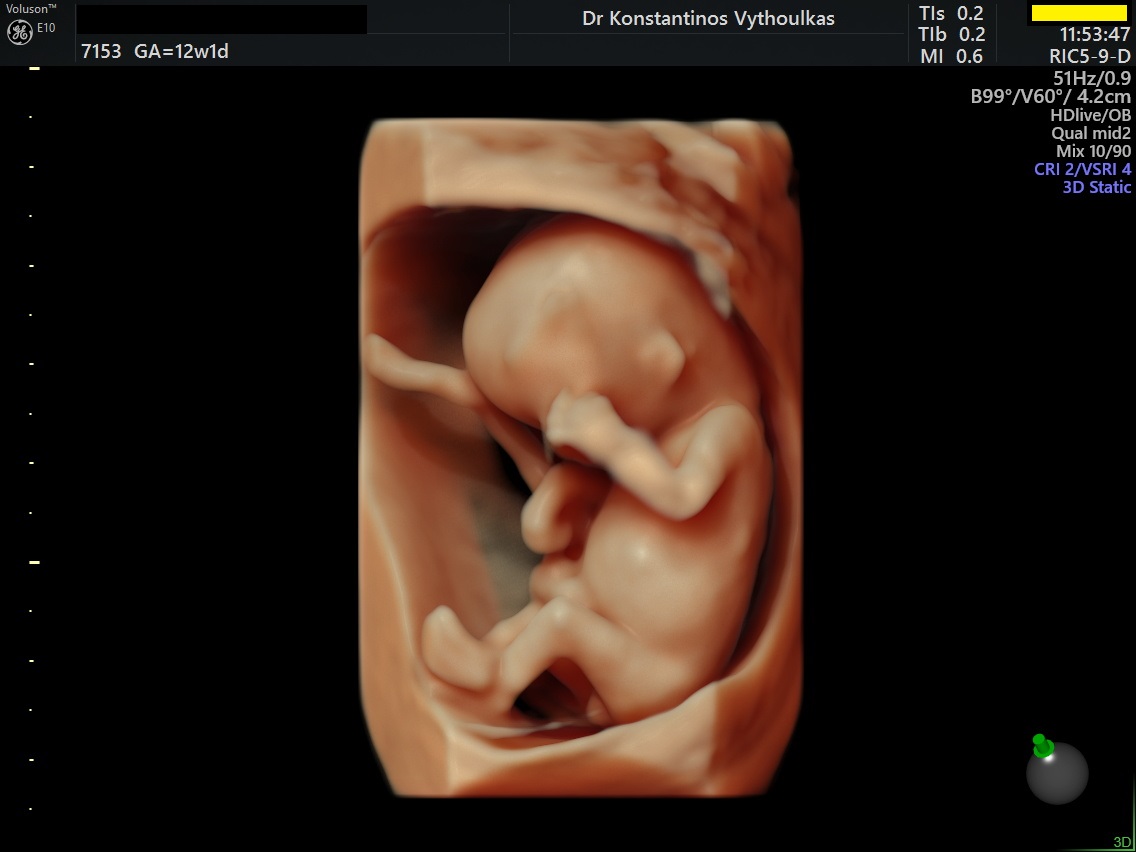

Φωτογραφίες από το αρχείο και από το χώρο του ιατρείου του γυναικολόγου Βυθούλκα Κωνσταντίνου, καθώς και του εργαστηρίου της κυτταρολόγου Λιβέρη Κατερίνας.